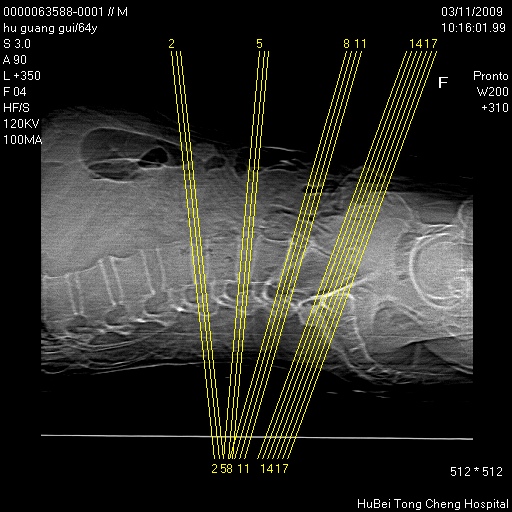

患者 男,64岁。腰痛十余天。(临床未提供其他病史)

临床诊断:腰痛原因待查(腰椎间盘突出症?)。

腰椎间盘ct轴位平扫(层厚5mm,层距4mm),图像如下: